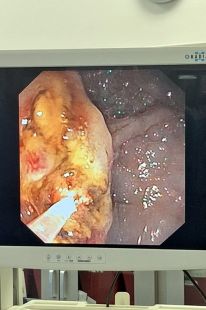

Pierwszy taki zabieg w Polsce i jeden z pierwszych w świecie

Zabieg był jednym z pierwszych na świecie